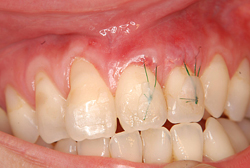

症例1【50代女性】主訴・前歯4本の根が見えるのが気になる。根面被覆(Root coverage)口蓋(上顎)から歯肉を採取し、露出している根面に歯肉を移植し被覆。

術中

根面被覆(Root coverage)口蓋(上顎)から歯肉を採取し、露出している根面に歯肉を移植し被覆。

露出が目立たなくなり、歯肉のラインもきれいに改善された。